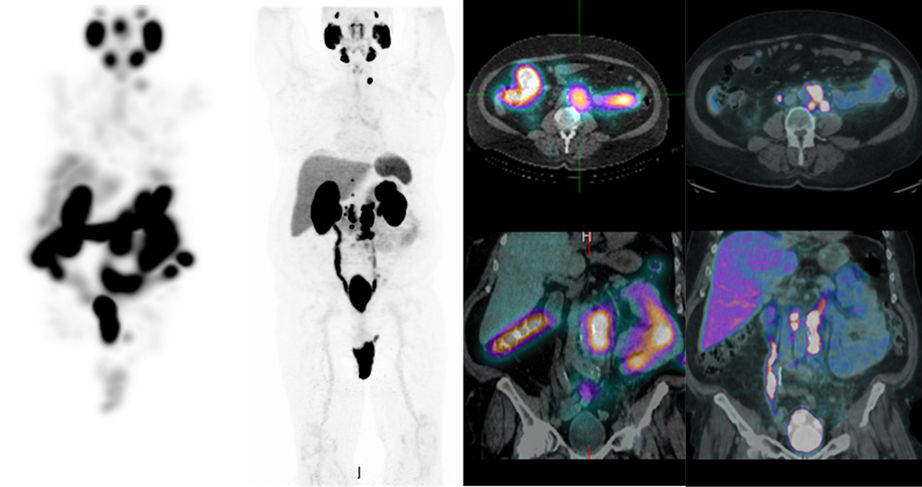

Pluvicto es una terapia innovadora de medicina nuclear indicada para pacientes con cáncer de próstata metastásico resistente a la castración (mCRPC). Utiliza Lutecio-177 unido a PSMA, un marcador presente en las células cancerosas de próstata, para administrar radiación de forma precisa directamente al tumor.

Con Pluvicto, se logra:

Atacar selectivamente las células cancerígenas sin dañar en gran medida los tejidos sanos

Reducir la carga tumoral y controlar la progresión del cáncer

Ofrecer una opción terapéutica avanzada para pacientes que ya han recibido otros tratamientos